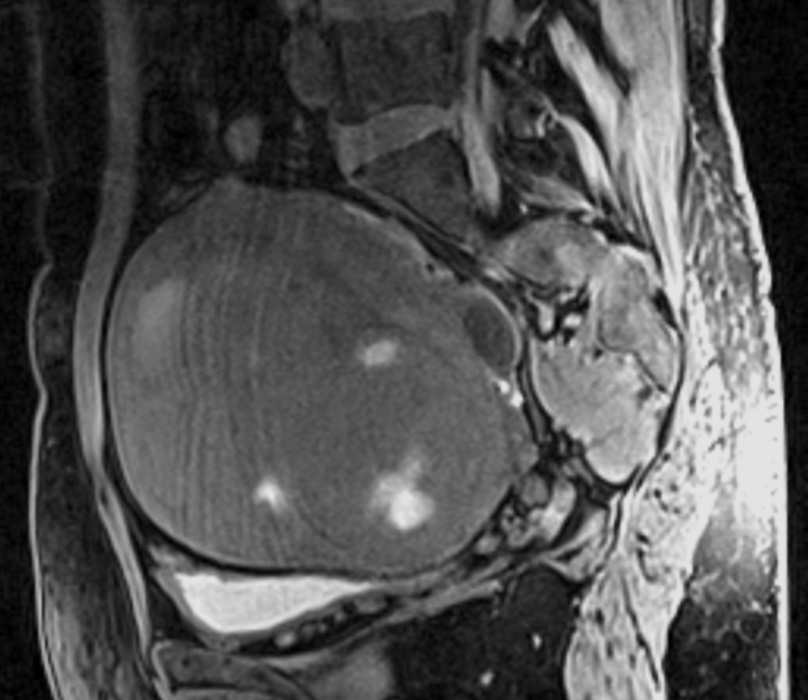

При поступлении пациентке проведено МРТ органов малого таза с контрастированием (рис. 1). По данным МРТ: по передней стенке матки интерстициально расположены 2 узла: 73×72×72 мм вентральный и 58×44×50 мм дорзальный, оба обладают значительным масс-эффектом с деформацией полости органа; по задней стенке, ближе к дну органа, аналогичного характера миоматозные узлы до 16×15×10 мм преимущественно субмукозной локализации.

Рис. 1. Клинический пример №1. МРТ с контрастированием до проведения ЭМА. / Fig. 1. Clinical case 1. Contrast-enhanced MRI before UAE.

Яичники расположены типично: правый – 34×17×17 мм с фолликулами до 14 мм, левый – 42×21×18 мм с фолликулами до 16 мм. При оценке DWI/ADC – без особенностей. При оценке постконтрастных серий отмечается негомогенное накопление контрастного вещества в структуре миоматозных узлов тела матки.